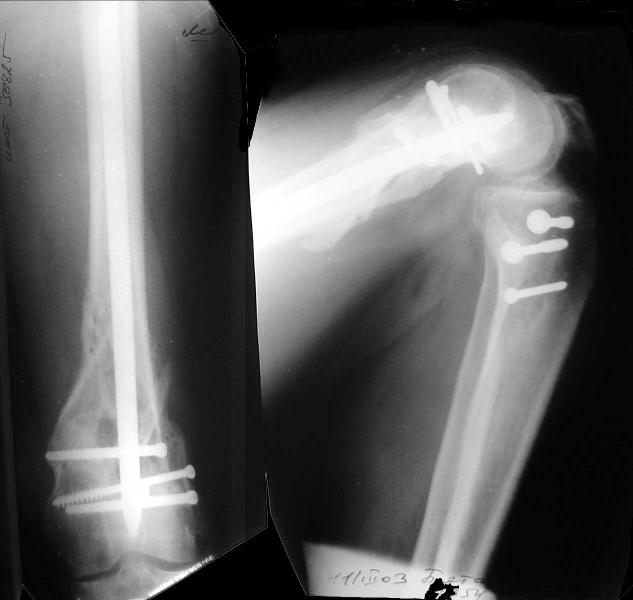

This is what we have done... As generally true for LISS look at the bone not the hardware.

There are two more srews above. The one not completely in got damaged head.

And why LISS is superior here than nail?

Look what we would have done.

I would not say that the LISS is superior to the nail. If I would, I had not post original mail. I wanted to generate discussion. Your option is a very viable one. I feel a little bit shaky the distal femur, but it is just gut feeling no science behind it. Any way nice fixation, congarts!